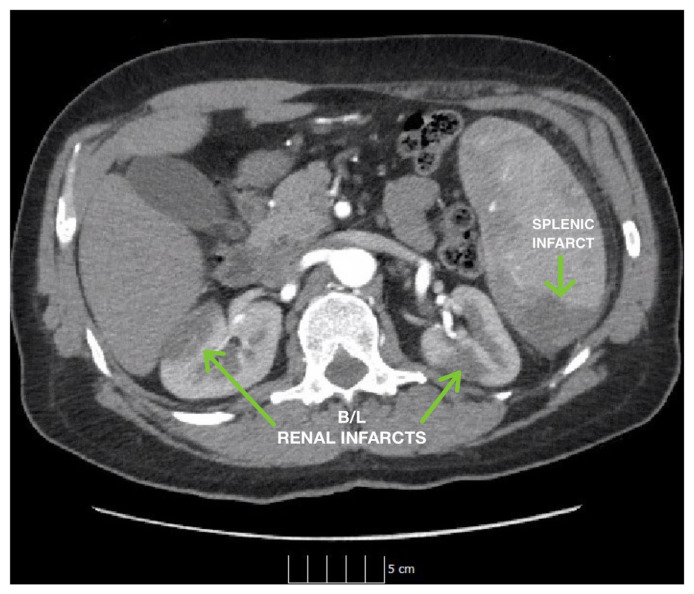

Abstract Image